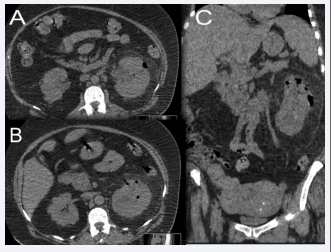

Axial sections (A, B) and coronal reconstruction (C) of an  abdominal CT scan without intravenous contrast injection showing air  bubbles at the pyloric, intra-parenchymal and peri-renal level of the left  kidney. The appearance is compatible with a class 3A left EPN according  to Huang et al

Figure 10: Axial sections (A, B) and coronal reconstruction (C) of an abdominal CT scan without intravenous contrast injection showing air bubbles at the pyloric, intra-parenchymal and peri-renal level of the left kidney. The appearance is compatible with a class 3A left EPN according to Huang et al